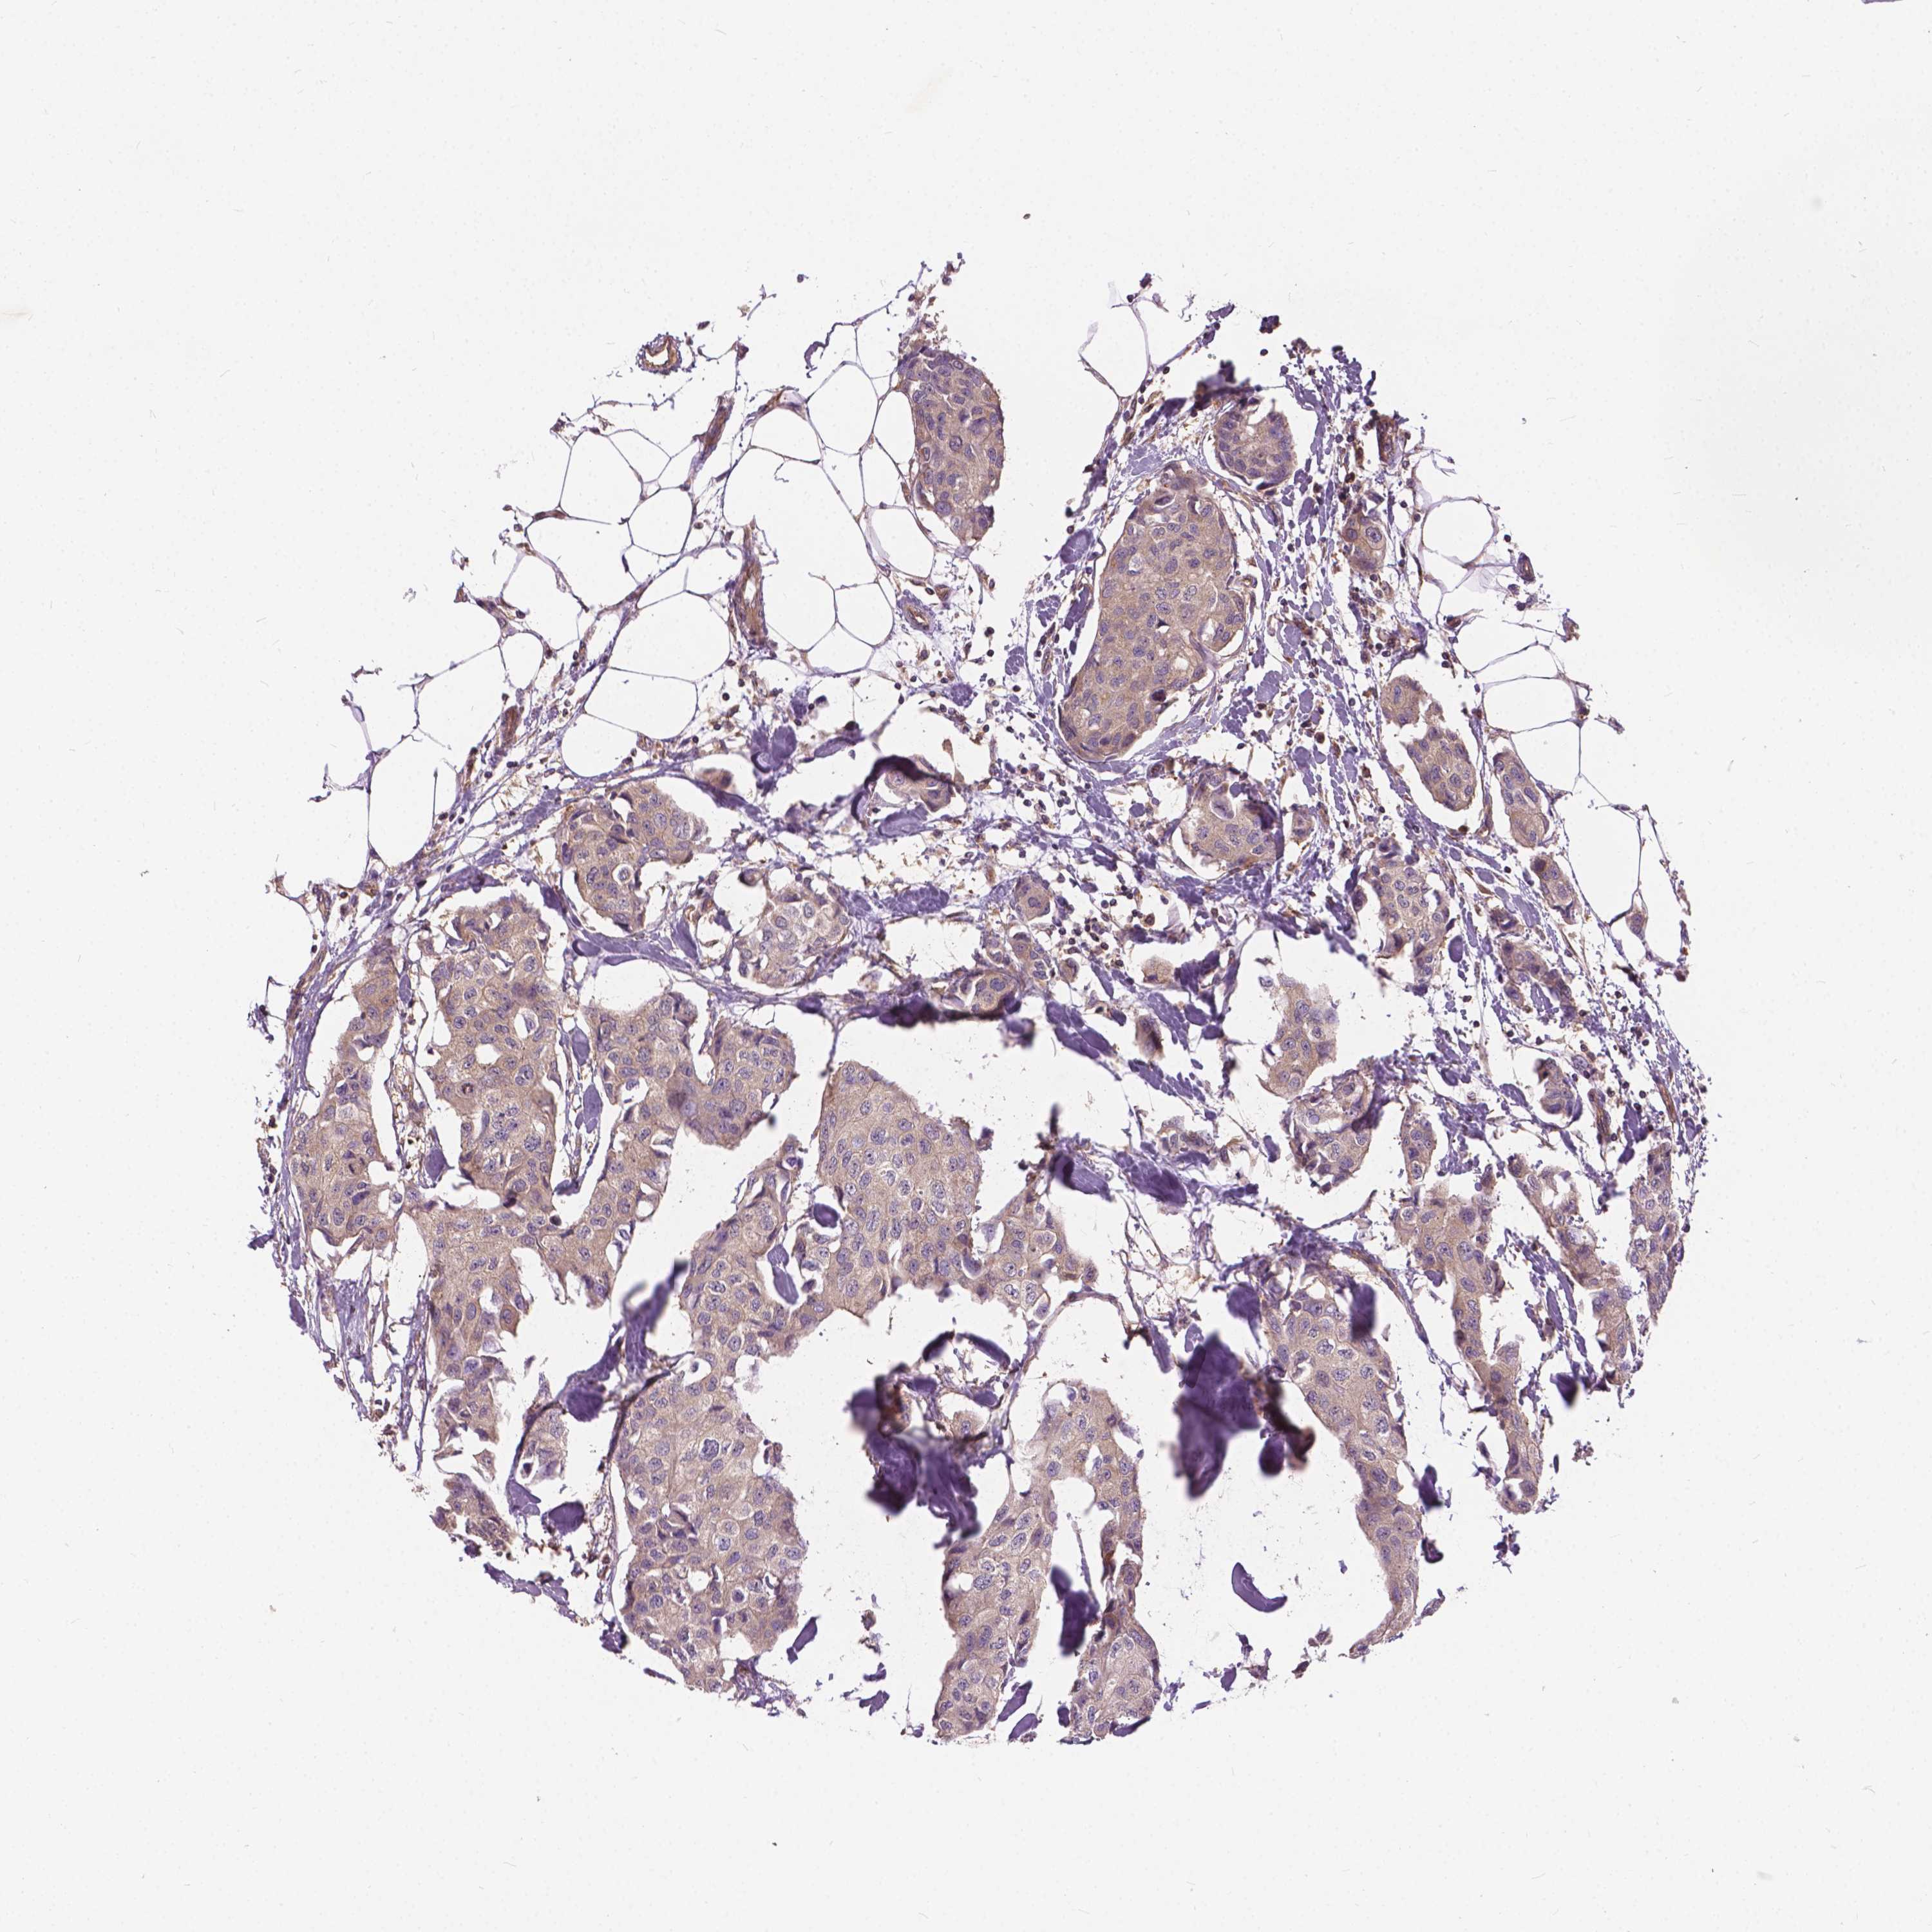

CANCER BREAST CANCER Show tissue menu

BRCA TCGA BRCA VALIDATION PROTEIN EXPRESSION